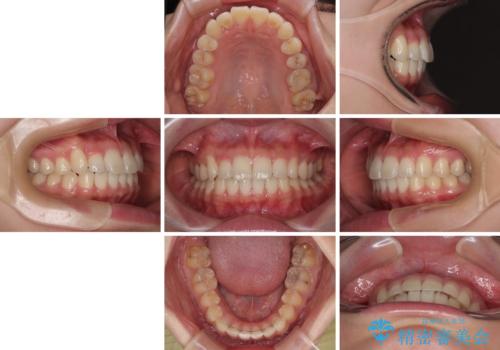

- 上下前歯のデコボコを気にして来院された患者様です。

ワイヤー矯正でもマウスピース矯正でも可能でしたが、短期間で、自身の手を煩わせることなく治療を行いたいとのことで、ワイヤー装置にて矯正治療を行うこととしました。

僅か8ヶ月という短期間で、綺麗な歯列に仕上がりました。